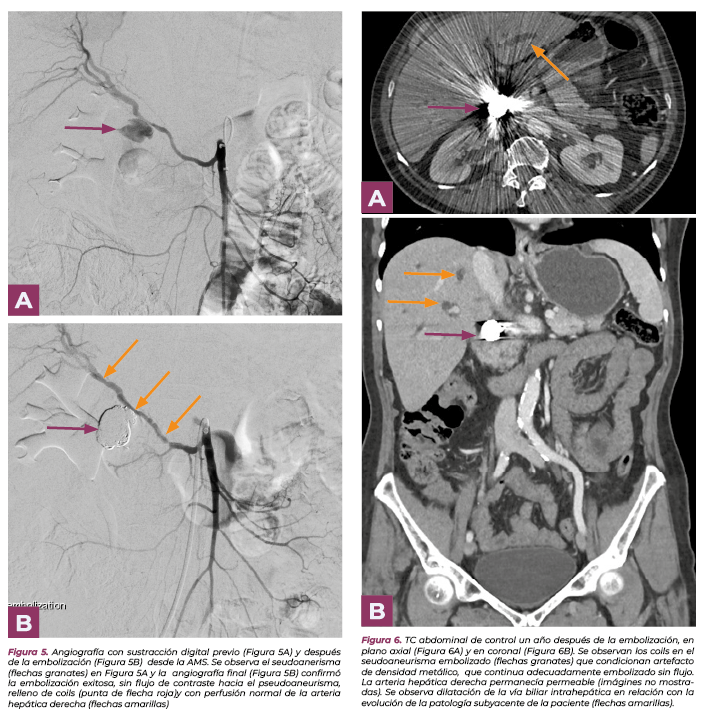

Se finaliza (Fig.5) cuando se considera que el PAH está adecuadamente embolizado, se prodece al desinflado y retirada del catéter balón y microcatéter, confirmado en la arteriografía final que se ha trombosado adecuadamente el PAH con preservación del flujo en la arteria hepática derecha.

Se le realizaron estudios de imagen de control. En TC de control al año (Fig.6) se visualizan los coils, que no se han modificado, y que condicionan artefacto metálico que dificulta la valoración, el pseudoaneurisma permanece embolizado y la arteria hepática derecha permeable, se observa además progresión de su enfermedad basal, por crecimiento del colangiocarcinoma y dilatación de la vía biliar intrahepática.